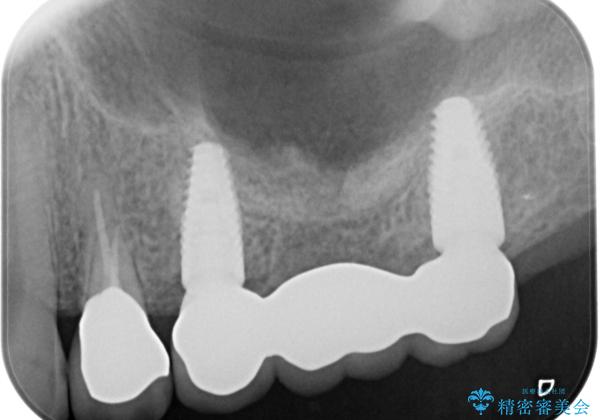

奥歯がない 咬合力を回復するインプラント治療

- 奥歯を虫歯で失ってしまい、しっかりと噛めるようになりたい、と希望され来院されました。

3本の歯(クラウン)を2本のインプラントで支えるインプラントブリッジによる咬合機能の回復を計画します。

また十分な骨の厚みを確保するためソケットリフト法を併用し、長期的な安定を見込めるインプラント治療を実践します。

治療後、しっかりと咬合機能が回復され見た目の自然さにも満足いただくことができました。